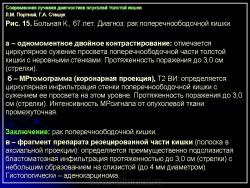

Протокол исследования включал применение импульсных последовательностей (ИП): SE в режиме Т1 с компенсацией дыхания, FSE, STIR (Т2 с синхронизацией дыхания). Основными МРсимптомами опухолевого поражения стенки кишки являются: неравномерное ее утолщение на ограниченном протяжении с соответствующим сужением просвета кишки, наличие внутрипросветного образования с неровными очертаниями и из менением МРсигнала (рис. 14). Толщина пораженной стенки кишки составляла от 7 до 40 мм. Очертания внутренних контуров стенки на уровне поражения были не ровные, бугристые. Интенсивность МРсигнала от из мененной стенки как на Т1, так и на Т2 ВИ была промежуточной (рис. 15), однородность сигнала зависела от преобладания процессов, развивающихся в опухолевой ткани: при имеющихся зонах распада на Т2 ВИ выявлялись очаги повышенной интенсивности МРсигнала. При использовании программы STIR интенсивность сигнала от опухолевой ткани была высокой. Распространение опухолевой инфильтрации за пределы стенки кишки характеризовалось нечеткостью наружных границ опухоли, сетчатым рисунком клетчатки с гетерогенным изменением Мрсигнала, более выраженным на Т1 ВИ (рис. 16б). При прорастании опухоли в смежные органы и структуры не визуализировались границы между измененной стенкой кишки и органом, на который распространялась опухолевая инфильтрация (рис. 17).